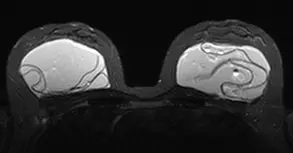

Nos casos de síndrome ASIA, é necessário retirar toda a cápsula, pois ela pode apresentar resquícios da prótese de silicone e se evita a contaminação dos tecidos mamários por silicone nos casos de ruptura. Nos laudos de anatomia patológica da cápsula, é possível verificar alterações normais frente à prótese de mama (Figura 1) e evidência de silicone nas cápsulas (Figura 2).(20)

Figura 1. Resultados considerados normais para biópsia de cápsula de prótese de mama. Fonte: elaborada pelo autor.

Figura 2. Evidência de material de prótese mamária (silicone) na biópsia da cápsula. Fonte: elaborada pelo autor.